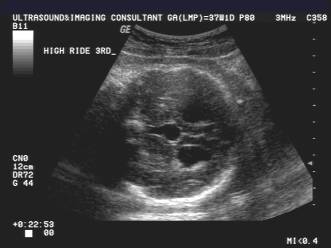

Interhemispheric cyst,high-riding 3rd ventricle |

Interhemispheric fissure adjoins the 3rd ventricle |

o

Absence

of the cavum septi pellucidi, upward displacement and enlargement of the third

ventricle